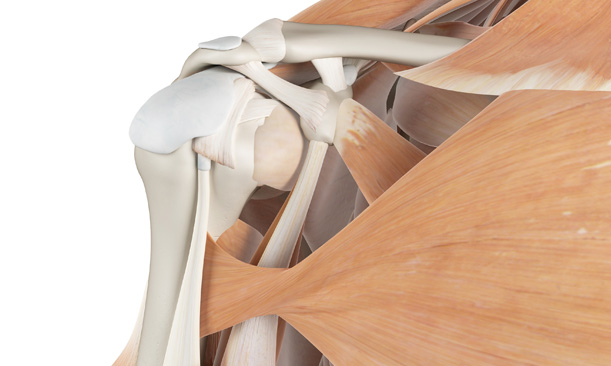

어깨충돌증후군이 발생하게 되면 회전근개에 염증이 발생하게 되고

급성 부종을 일으키게 됩니다.

어깨충돌증후군은 팔을 지속적으로 들고 일을 하는 직업군과

어깨를 많이 쓰는 스포츠 활동군에서 많이 발생합니다.

어깨의 휴식을 취하지 않고 무리하게 사용하는 경우 발생됩니다.